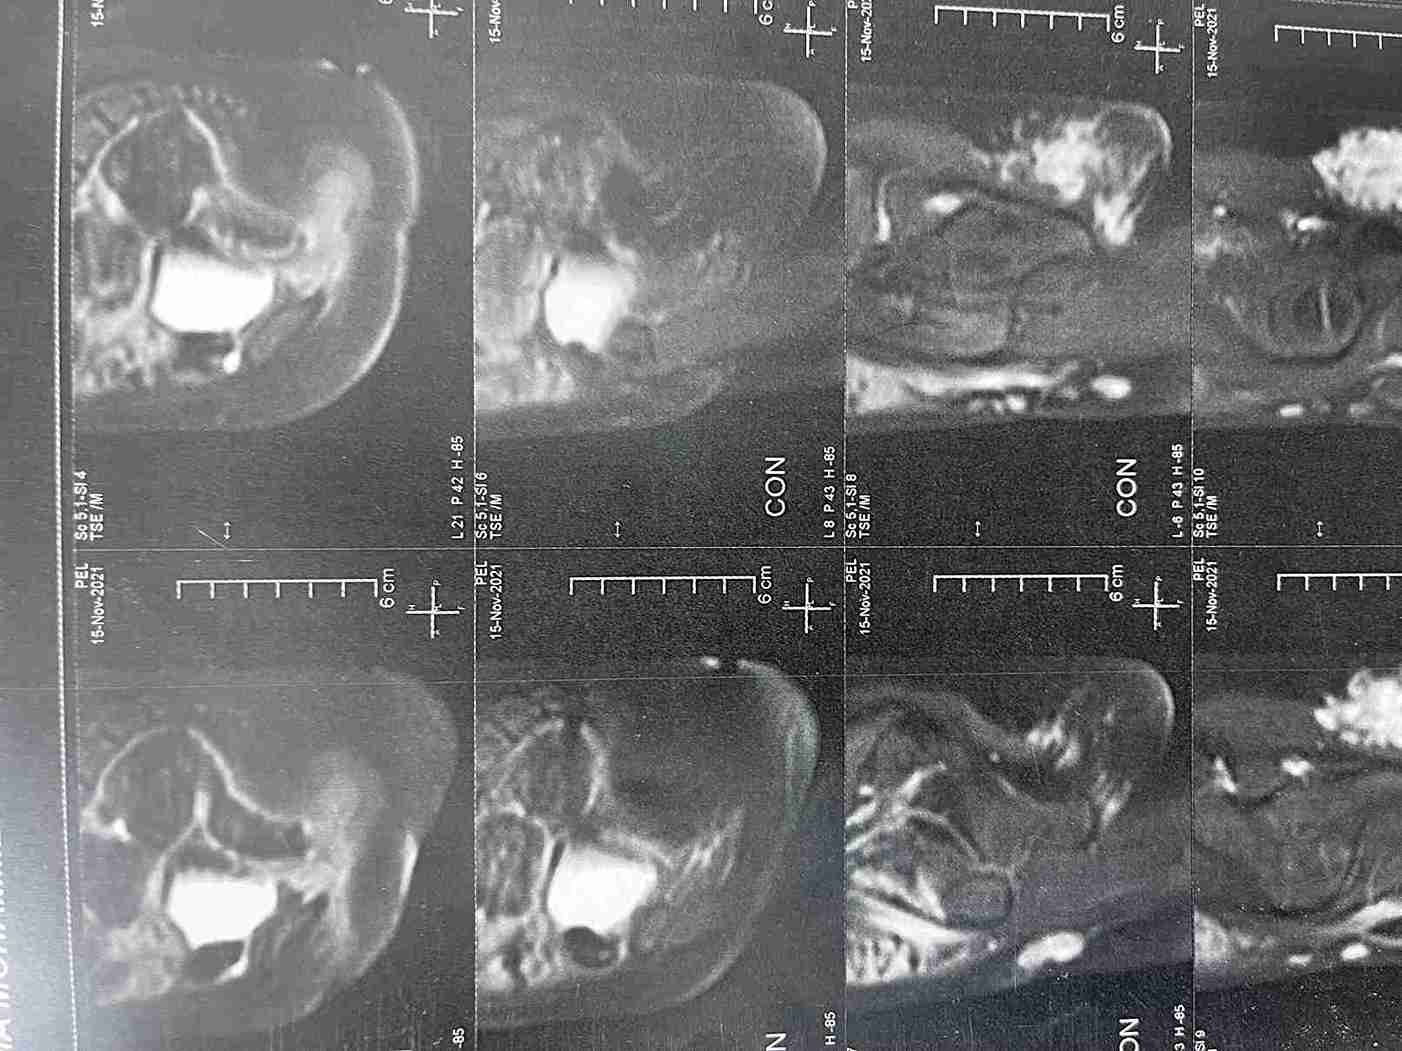

ورم بغلاف عصب عرق النسا الايمن بطفلة خمس سنوات ونصف

tumor in the right sciatic nerve in a five-and-a-half-year-old girl

Surgery for a Schwannoma on the Sciatic Nerve in a Child

This case involved the successful removal of a rare, benign tumor from the sheath of the right sciatic nerve in a 5.5-year-old girl. The tumor was causing pain in the thigh and buttock area. The surgery was performed with complete success, fully preserving the nerve's function.